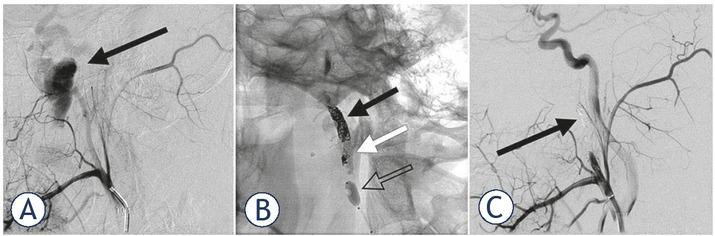

The patient was transferred to the neurointerventional suite and a standard right transfemoral vascular access was established. Digital substraction angiography (DSA) showed a laceration of the left ECA with an ensuing 3 × 4 cm pseudoaneurysm continuing into the proximal part of the left IMA (Figure 3A). DSA also showed a right SPA laceration with two small accompanying pseudoaneurysms (Figure 4A). The two culprit arteries were then superselectively catheterized and embolized. ECA embolization was performed using platinum coils and PHIL 25, while the SPA was embolized with PHIL 25 only (Figures 3B and 4B). In the case of the ECA embolization, coils created a mesh scaffold acting as a thrombogenic locus, and PHIL was then added to form a coagulopathy-independent lumen-obliterating cast. PHIL was chosen over other available liquid EAs for its ready-to-use characteristics, saving precious time in an emergency setting. In addition, its lava-like polymerisation properties ensured a well-controlled application, helping prevent any inadvertent injection into the dangerous ECA-internal carotid artery and ECA-vertebral artery anastomoses.

(A) A lateral left ECA angiogram showing ECA laceration with 3 × 4 cm pseudoaneurysm continuing into the proximal part of the left IMA. Contrast extravasation can be observed in the vicinity of the pseudoaneurysm. (B) A fluoroscopic view showing left ECA embolization using coils (black arrow) and PHIL 25 liquid embolization agent (white arrow) under balloon flow control (empty arrow). Also of note area small number of stray coils anchored in the vessel in the region of PHIL application (white arrow). (C) A post-embolization lateral left ECA angiogram showing complete exclusion of the ECA distally to the facial artery (black arrow).

Effort was made to embolize at or just proximal to the laceration point in order to preserve proximal arterial territories. Embolization was continued to the point of arterial stasis. Due to the well-developed left ECA and the resulting high blood flow to the pseudoaneurysm, the ECA embolization was performed under flow control provided by temporary proximal balloon occlusion. No flow control was needed for the SPA embolization. The embolizations of both lesions were immediately followed by complete cessation of the ear bleeding.

Postembolization imaging showed total exclusion of the lacerated vessels (Figures 3C and 4C), complete patency of all proximal vessels, no collateral pathways to the pseudoaneurysm and no other origins of bleeding. There were no procedure-related complications.